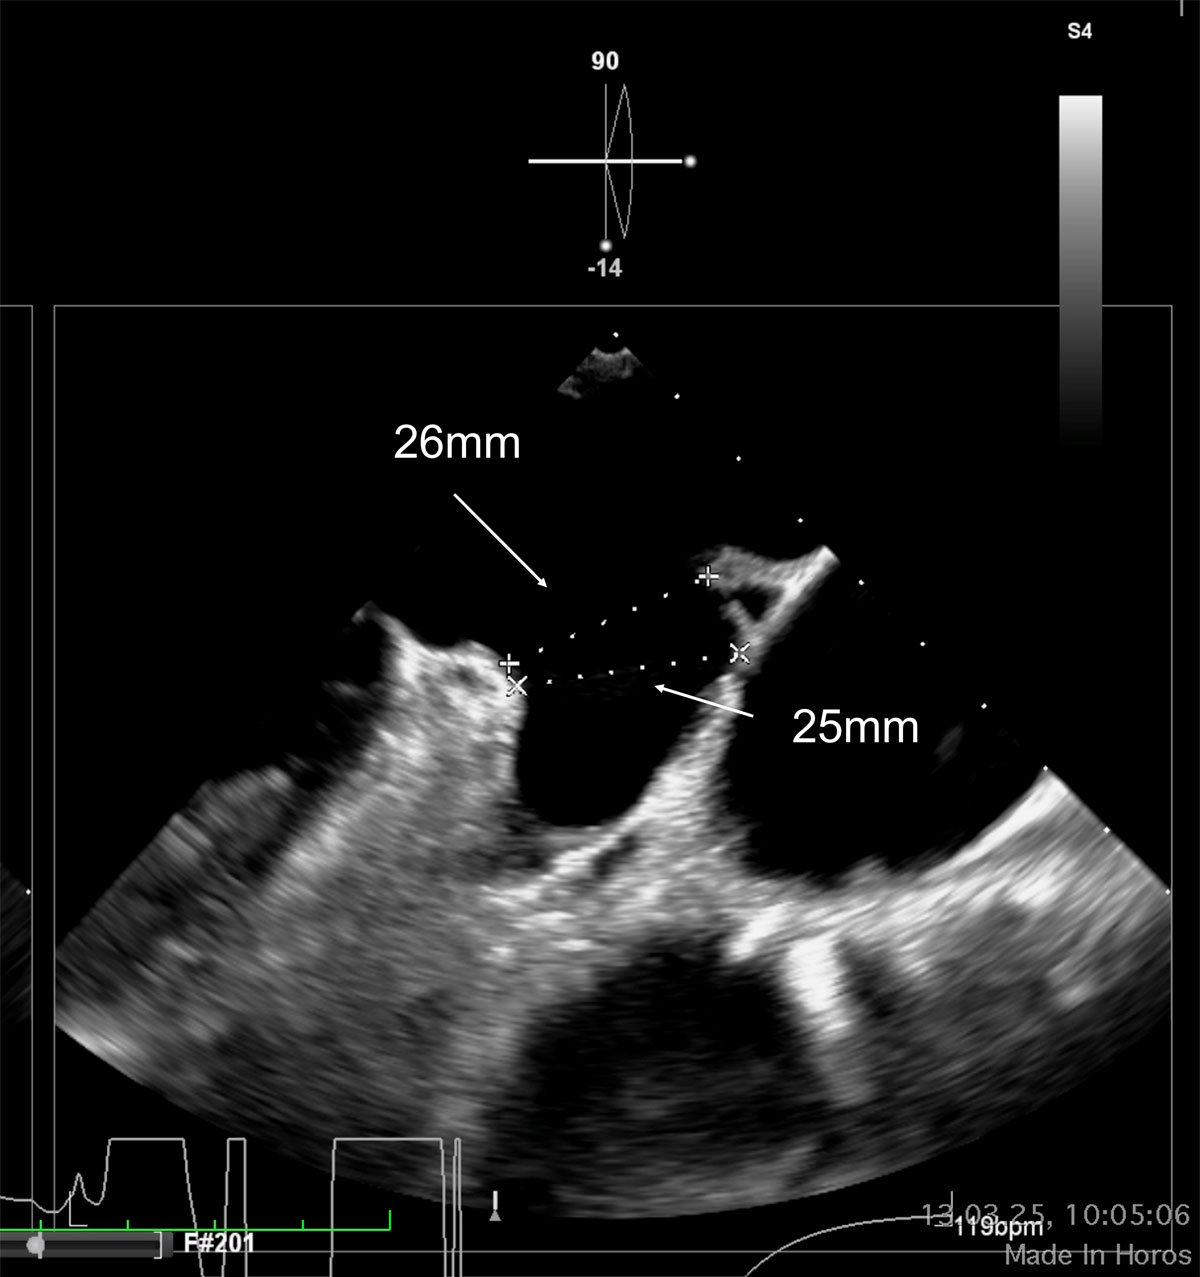

LAA closure - TOE sizing 0°/90°

LAA closure - sizing 0°/90°

We have a chicken wing left atrial appendage morphology, with a landing zone maximum diameter within the 25-26 mm range, according to imaging tests. In these anatomies, I use to carefully assess the ostium diameters, which are not provided in this case, and I choose a disc approximately 10 mm larger in diameter than the ostium to ensure a complete seal, if the surrounding structures allow it. If using the Amulet device, the most appropriate implantation in this case would be obtained by a semi-sandwich technique, with a 31 mm device and a 38 mm disc. Again, this last aspect is crucial in this scenario to ensure a proper seal.